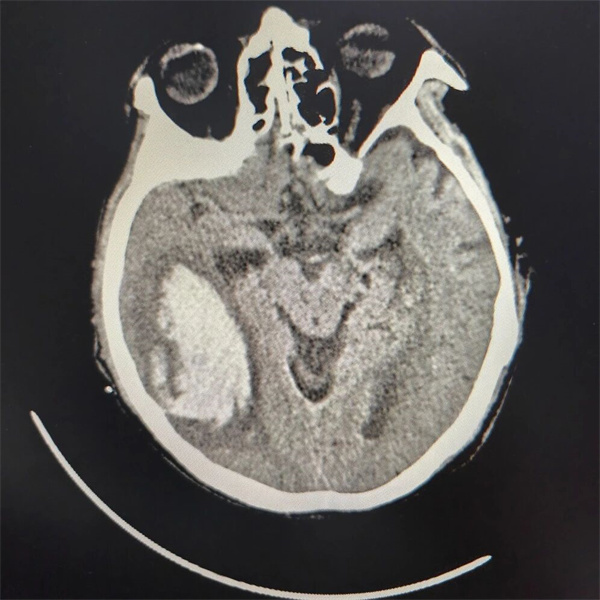

3小时显微手术清血肿,颅内压回归安全数值

手术灯亮起的瞬间,一场与死神的“近身搏斗”正式展开。老年患者的脑组织本就脆弱如绵,加之血肿长期压迫导致解剖结构移位,精准定位血肿腔成为首要难题。神经外科团队成员各司其职,吸除血肿、止血、保护功能区,每一个动作都沉稳有序。经过3小时的紧张奋战,颅内83.7ml血肿被彻底清除,颞肌下减压术为肿胀的脑组织“松了绑”,颅内压监测电极成功植入,实时数据显示颅内压从术前的35mmHg降至15mmHg以下——这一安全数值的出现,意味着生命体征已逐步平稳。当老人的自主呼吸开始逐渐恢复时,手术室里响起了压抑许久的掌声。这掌声里,有对生命的敬畏,更有对团队协作的致敬。

▲ 术后患者头颅CT影像